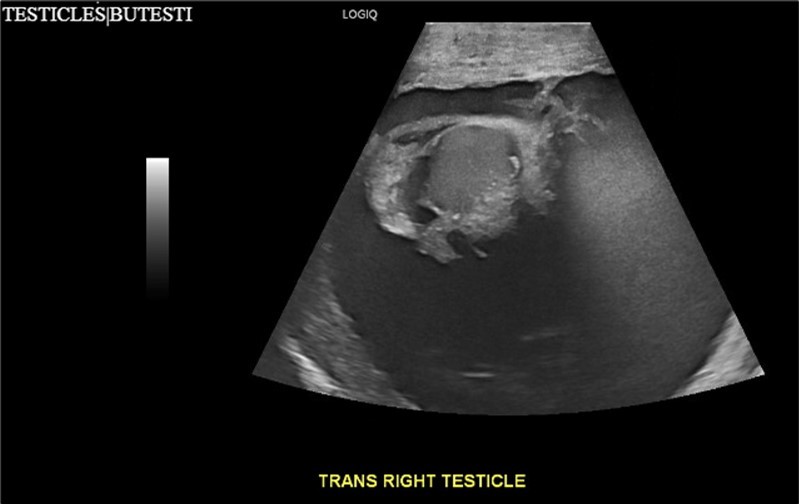

A 34-year-old male presented to the Emergency Department with complaints of large right-sided scrotal swelling, accompanied by scrotal discomfort. The patient’s past medical history was remarkable for a right-sided inguinal hernia, which had been present for several years and was repaired via right open herniorrhaphy with mesh placement three months prior. Physical examination prior to the herniorrhaphy revealed a large inguinoscrotal swelling, measuring 5 inches by 6 inches. During the herniorrhaphy, a very large hernia sac was encountered that could not be fully dissected from the cord structures and required placement of two large meshes; however, the testicles were successfully reduced back into the scrotum. Ultrasound of the right testicle revealed a large hypoechoic space with a complex collection and posterior displacement of the testicle, indicating a possible hydrocele (Figure 1, Figure 2, Figure 3, Figure 4). The patient was taken to the operating room for a right hydrocelectomy. During the procedure, it was noted that the penis was buried within the scrotal swelling, necessitating the placement of a Foley catheter to identify surrounding structures. Upon incision through the Dartos fascia, significant fibrotic tissue and fluid were encountered, making it difficult to maneuver around the hydrocele sac. Upon incising the hydrocele sac, a large collection of thick, dark brown fluid resembling old blood clots was immediately aspirated. Approximately 2 liters of fluid were drained from the sac. After identifying the testicle and cord structures, the proper placement of the testicle within the scrotum was verified. Due to excessive scrotal skin, a scrotoplasty was performed prior to suturing the scrotal skin and fascia (Figure 5). The postoperative hospital course was unremarkable. The patient was discharged with plans to return to the clinic for follow-up with the surgeon.

Figure 2.Ultrasound imaging in the transverse plane of the right testicle.